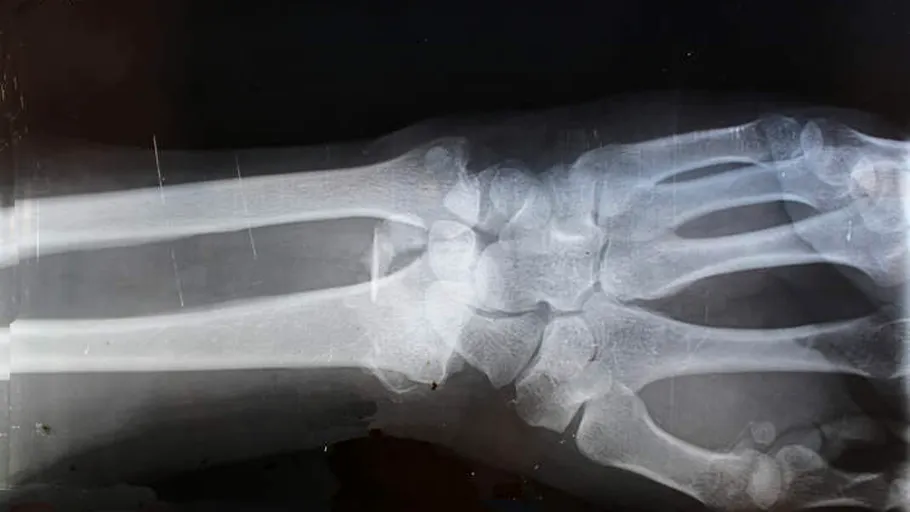

Inventatorii au prezentat un caz experimental al unui pacient cu fractură la încheietura mâinii. El a primit o injecție printr-o incizie de doar trei centimetri. Fragmentele osoase s-au unit în trei minute, evitând o intervenție chirurgicală complexă cu plăci și șuruburi metalice. În mod normal, o astfel de operație ar fi necesitat o a doua intervenție pentru scoaterea plăcilor după un an. La controlul de trei luni, fractura era complet vindecată și fără complicații. Inventatorii subliniază că lipiciul pentru oase Bone-02 a fost aplicat cu succes în peste 150 de cazuri documentate.